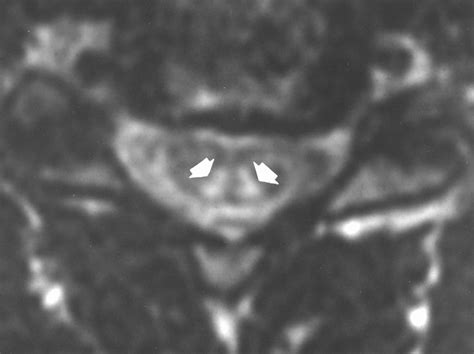

• Magnetic Resonance Imaging (MRI): To visualize the spinal cord and brain for signs of degeneration.

• subacute combined degeneration on mri